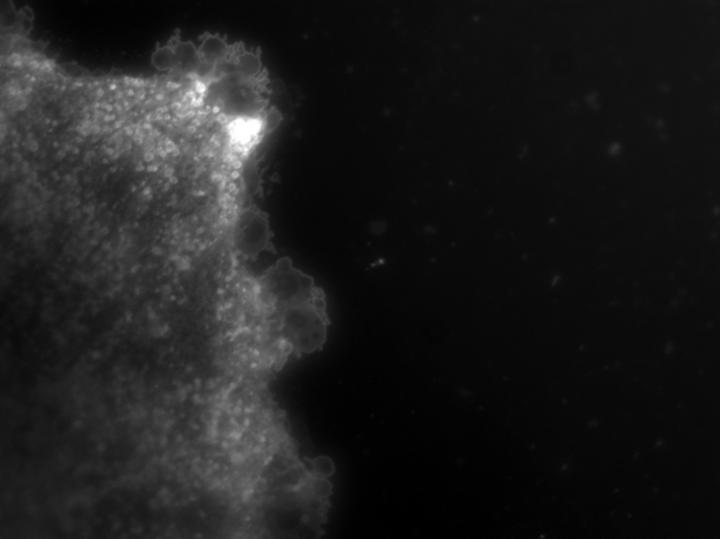

image: Vesicles are being released from an astrocyte in the brain. view more

Credit: Norm Haughey's laboratory

In their new study, described in Science Signaling April 13, Johns Hopkins researchers say there is evidence that vesicles or small (about the size of a virus), fat-like molecules and protein-filled sacks released from a type of immune cell in the brain called astrocytes travel through the bloodstream to the liver. The liver then instructs white blood cells to go to the site of injury in the brain.

He read earlier studies showing that the enzyme nSMase2 was required for forming and releasing exosomes. Exosomes form inside cell compartments and release outside the cell when these compartments fuse with the cell's surrounding membrane. Exosomes are surrounded by bits of cell membrane and filled with proteins and different types of the genetic material RNA.